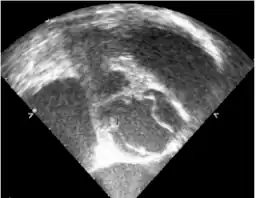

Transesophageal echocardiography- the right side commissure of the bicuspid aortic valve is ruptured -